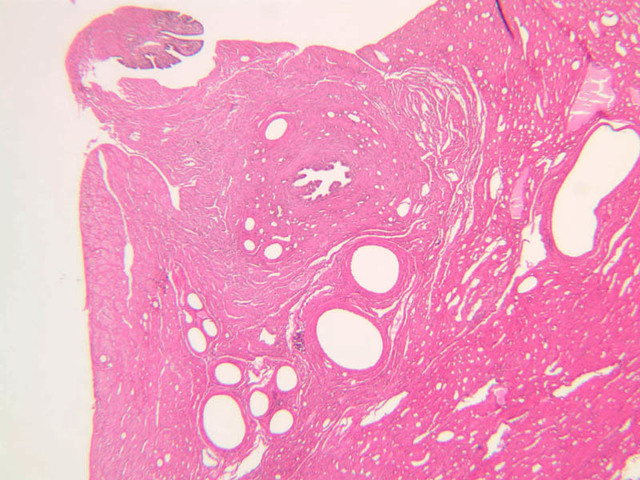

The resting or inactive mammary gland consists of predominantly dense connective tissue with small clusters of ducts and a few glandular elements (slide A-93 [2.5x-labeled, 10x, 20x, 40x] [1x, 2.5x, 10x, 20x]). It is difficult to differentiate between small ducts and alveoli as each is lined by simple low cuboidal cells. Lobes and lobules are not well defined. During puberty, predominantly under the influence of the ovarian hormone estrogen, the glandular or epithelial ducts proliferate and begin to differentiate into clusters of ductal and alveolar units termed terminal ductal lobule units (TDLUs). The non-pregnant gland will form multiple TDLUs that will not fully differentiate until pregnancy-induced growth. TDLUs are classified into Type I, Type II and Type III based on density of the ductules within each lobular unit. Type I and Type II lobules are typical of inactive glands that have not undergone a pregnancy cycle. Type III lobules are seen only in active glands or in inactive glands that have been through a pregnancy. Intralobular connective tissue is loose connective tissue that surrounds the alveoli and ducts within a lobule. The interlobular connective tissue is dense and contains considerable adipose tissue.

During pregnancy, predominantly under the influence of the ovarian hormone progesterone and the pituitary hormone prolactin, the glandular elements proliferate and differentiate to form milk-secreting units. In later stages of pregnancy, alveolar development becomes prominent and the amount of connective tissue and adipose tissue decreases. The secretory cells hypertrophy and accumulate secretory product.

The mammary gland in its active state is a compound tubuloalveolar gland (slide A-92 [10x, 20x, 40x-labeled] [2.5x, 10x, 20x, 40x]; A-94 [2.5x, 10x, 20x, 40x]). At this time, the gland is predominantly glandular tissue. Each alveolus is lined by a simple cuboidal epithelium. At the base of these cells, and within the alveolar basal lamina, are the stellate-shaped myoepithelial cells that are highly contractile and function to facilitate milk ejection.